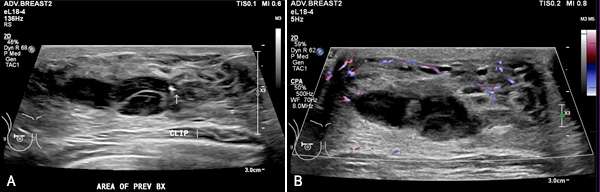

On ultrasound, hematomas can have variable appearance depending on the age of the blood products.

- Acute hematomas typically appear as hypoechoic fluid collections as acute blood products are less reflective to ultrasound waves compared to surrounding tissues. They may have well-defined or irregular borders depending on the integrity/composition of the surrounding tissue and typically have homogenous internal echogenicity. Color Doppler imaging may be useful in identifying an active bleed if a damaged vessel is visualized adjacent to a developing hematoma. Acute hematomas sometimes exhibit posterior acoustic enhancement.

- Chronic hematomas often appear more heterogeneous on ultrasound compared to acute hematomas because of the breakdown of blood components and the formation of fibrin. Chronic hematomas may form a fibrous capsule as the body attempts to encapsulate and contain the hematoma. Margins may be well circumscribed but may be partially indistinct due to the presence of internal echoes. Color Doppler imaging typically exhibits reduced vascularity as the body works to reduce blood flow at the site of a bleed. In contrast to acute hematomas, chronic hematomas may exhibit posterior acoustic shadowing due to the age of blood products within the hematoma which may produce internal echoes.